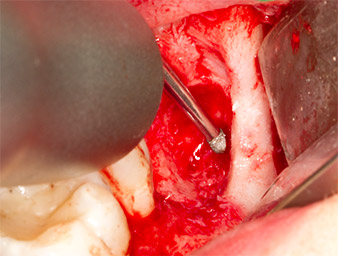

After block and local anaesthesia, the operating site was opened up and the soft tissue exposed for buccal retromolar access (Fig. 3).

The tissue above the root remnant was not completely ossified and consisted for the most part of granulation tissue modified by inflammation (Fig. 4).